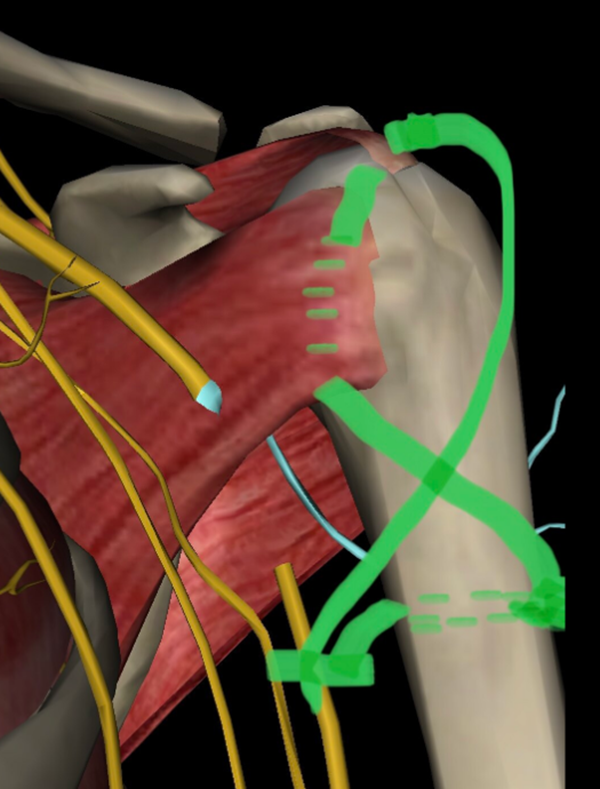

图1 内:肩胛下肌-小结节,外:冈上肌-大结节

冈上肌,冈下肌,小圆肌止于大结节,肩胛下肌止于小结节,这四个肌肉的肌腱包绕肩关节形成肩袖。大圆肌肌腱止于小结节嵴,位置在小结节下方,并不包绕肩关节。

图2 肩关节后面,冈上下肌与小圆肌止于大结节与嵴

图3 肩关节前面,肩胛下肌与大圆肌止于小结节与嵴

3、双套固定技术(团队推荐技术)

(2)骨折部位下方3~4cm,在肱二头肌腱沟两侧钻孔穿钢丝,3.2cm钻头横形钻孔,穿过2条钢丝,分别经冈上肌腱下方及大小结节,以2个“8”字形固定(或胸骨钢丝固定)。

图12 带针芯针穿过肩胛下肌腱、小结节、肱骨头,由复位的大结节和附着的肩袖处穿出,穿过钢丝,再经肱骨干近端横形孔穿过,8字拧紧固定

第一个“8”穿冈上肌腱下,固定大结节;

第二个“8”穿肩胛下肌腱下,固定小结节,再经肱骨头,再穿冈上肌腱下,固定大结节;分别经肱骨干近端横行孔穿过,“8”字打结固定。